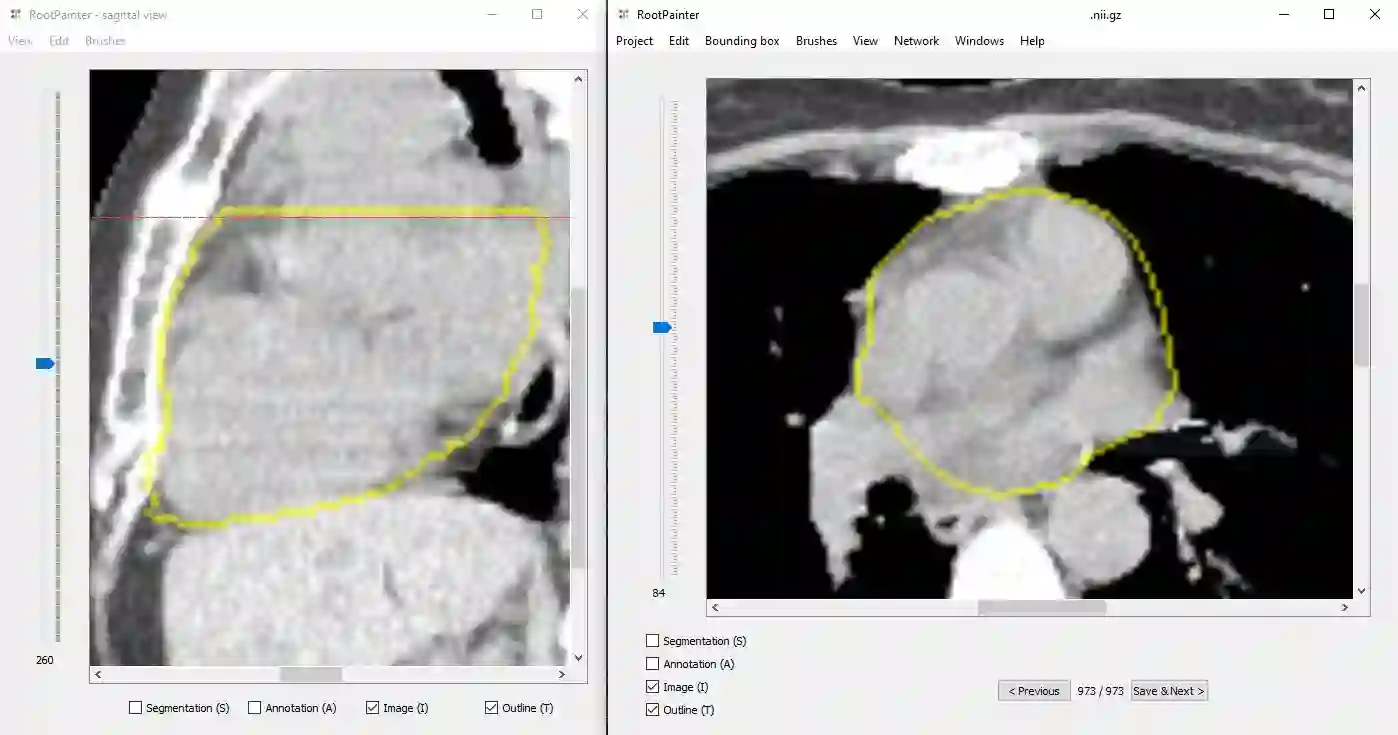

Organ-at-risk contouring is still a bottleneck in radiotherapy, with many deep learning methods falling short of promised results when evaluated on clinical data. We investigate the accuracy and time-savings resulting from the use of an interactive-machine-learning method for an organ-at-risk contouring task. We compare the method to the Eclipse contouring software and find strong agreement with manual delineations, with a dice score of 0.95. The annotations created using corrective-annotation also take less time to create as more images are annotated, resulting in substantial time savings compared to manual methods, with hearts that take 2 minutes and 2 seconds to delineate on average, after 923 images have been delineated, compared to 7 minutes and 1 seconds when delineating manually. Our experiment demonstrates that interactive-machine-learning with corrective-annotation provides a fast and accessible way for non computer-scientists to train deep-learning models to segment their own structures of interest as part of routine clinical workflows. Source code is available at \href{https://github.com/Abe404/RootPainter3D}{this HTTPS URL}.